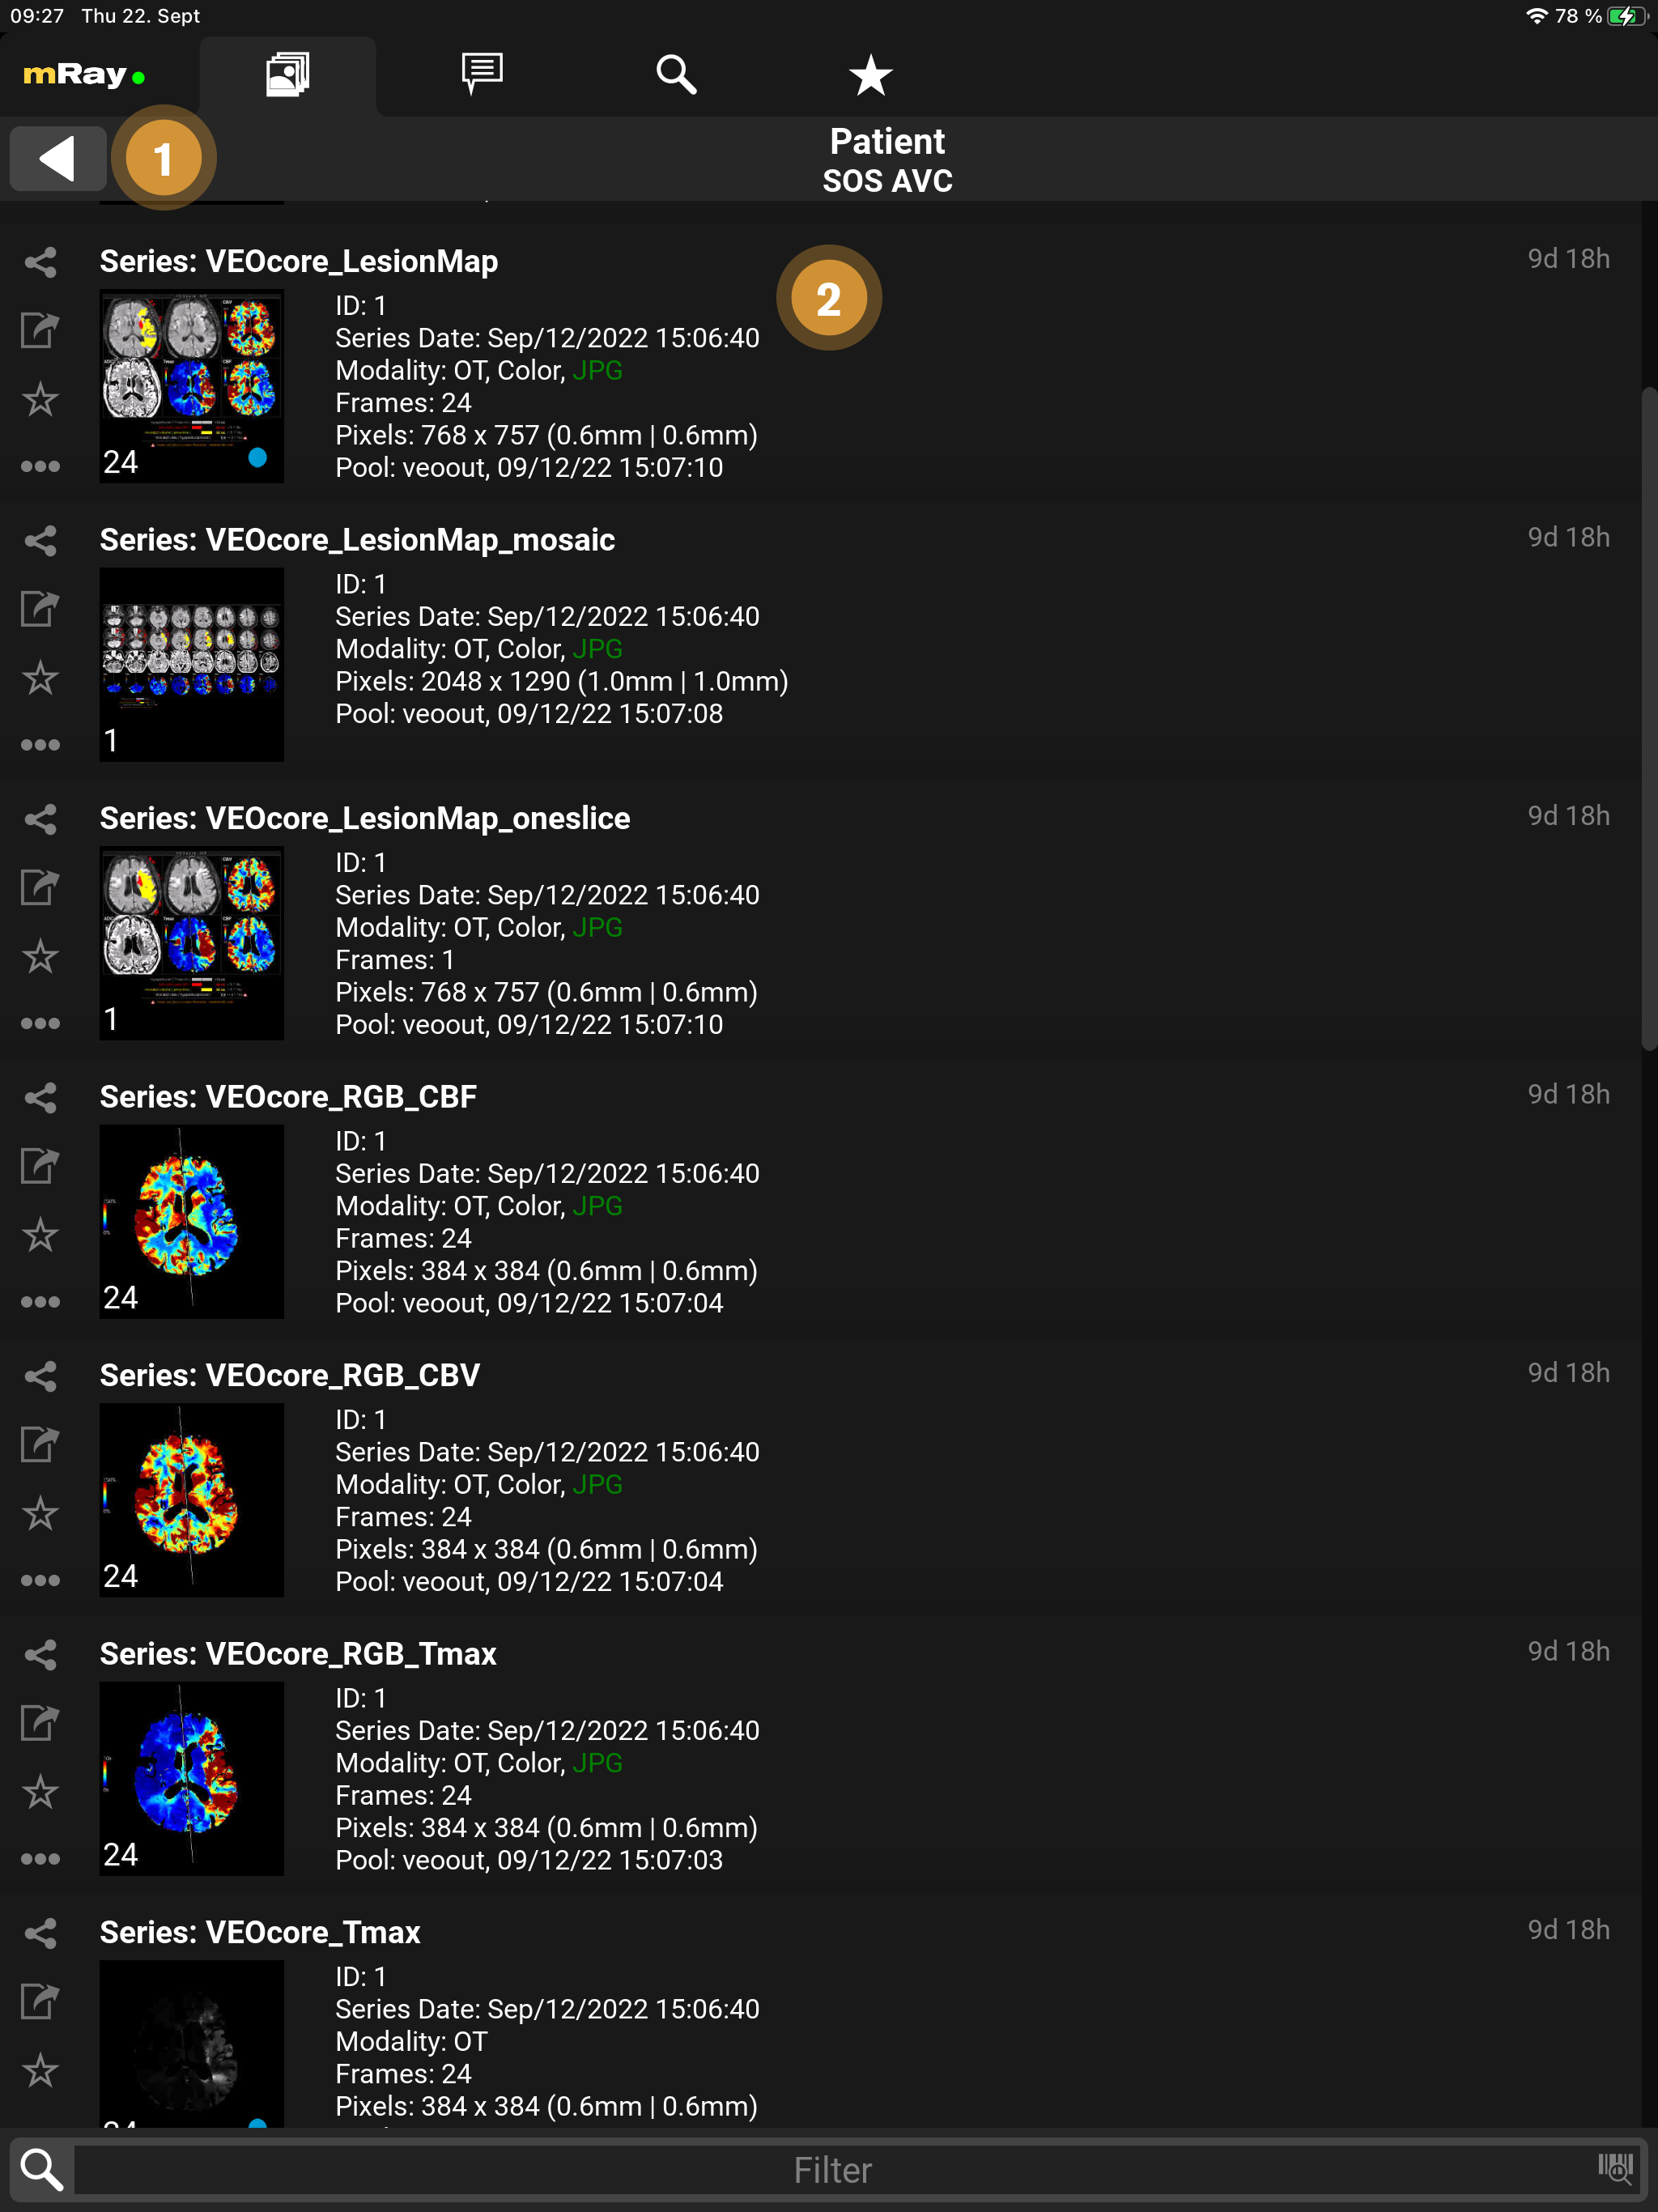

9.2. Serienauswahl

-

Zurück: Rückkehr zur Patientenliste.

-

Datensätze: Auflistung aller aufgenommenen Bilder der Studie des Patienten.

Durch Anklicken einer Serie wird diese heruntergeladen (falls nicht schon passiert) und zur Betrachtung geöffnet.

9.2.2. Serien Details

Mehr Details über eine Serie können Sie in der Serienauswahl einsehen.

Pool: Name des Datenpools; Zeitpunkt, wann die Serie in mRay verfügbar war; Transferzeit vom PACS zu mRay